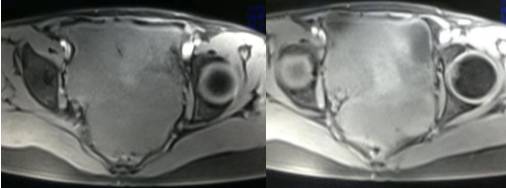

病理结果:黄体血肿

根据时间不同MR信号也有所不同,TIWI脂肪抑制序列可以鉴别脂肪和出血。

卵巢囊肿:呈均匀的T1WI 低信号,T2WI 高信号,边界清楚,壁薄,大多数病灶直径≤5 cm,但囊肿的起源及定性诊断困难。

功能性囊肿:因囊肿内容物成分不同,信号可有改变,随访观察数月后其信号和大小可出现变化或消失。

畸胎瘤:多呈囊性或囊实性,单房或多房状,囊内液体可有分层,实质由多胚层组织构成,MR 信号不均,肿块内见脂肪信号有利于畸胎瘤的诊断。

巧克力囊肿:常呈多发的单囊或多囊改变,病灶大小不等,囊壁厚薄不均,囊内信号复杂,囊内或各囊腔间血液因出血时期不同,信号常呈多样性,囊肿内反复出血、破裂,形成相互粘连的多房性囊肿,是其较为特征性的表现。

在鉴别卵巢畸胎瘤、出血性囊肿或巧克力囊肿时,MR 脂肪抑制T1WI 可明确肿块内高信号成分是脂肪还是出血,同时由于脂肪组织与非脂肪组织的共振频率不同,在两者交界处沿磁场频率编码方向出现化学位移伪影,但出血性囊肿与巧克力囊肿的鉴别有时较为困难。